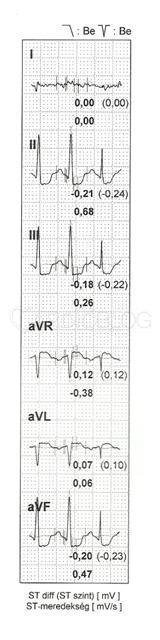

A beteg nyugalmi EKG-ján eltérés nem ábrázolódott. A terheléses EKG vizsgálat során a beteg mellkasi fájdalmat jelzett, V4-V6 szignifikáns STD, T-inverzió alakult ki.